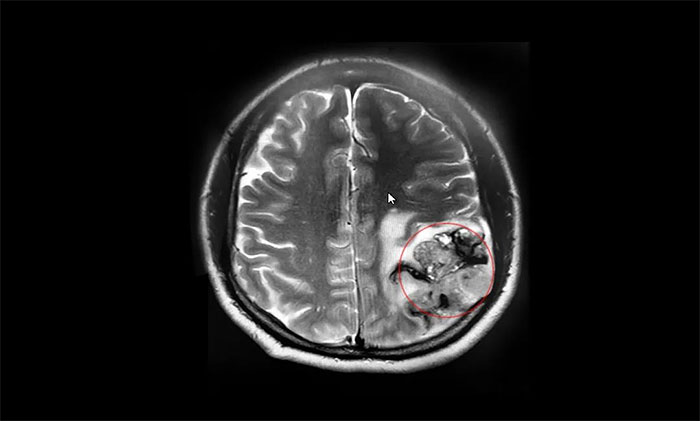

▲ MRI顯示腫瘤最大直徑超7厘米大小

因著這一線生機,張先生再次帶著妻子來到上海,轉入上海藍十字腦科醫(yī)院。入院檢查時,頭顱MRI平掃+增強提示:左側額頂葉占位性病變,最大徑約4.2×7.4×4.3cm,如鵝蛋般大小。